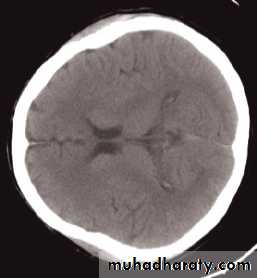

Computed tomography of the brain

• A routine CT examination of the brain involves making 20–30 axial sections.• The axial plane is the routine projection but computer reconstructions can be made from the axial sections, which then provide images in the coronal or sagittal planes

• The window settings are selected for the brain and are also altered to show the bones

The cardinal signs of an abnormality on a CT scan are:

• Abnormal tissue density• Mass effect

• Enlargement of the ventricles.

Abnormal tissue density

• Abnormal tissue may be of higher or lower density than the normal surrounding brain.• High density is seen with recent haemorrhage, calcified lesions, and areas of contrast enhancement

• Low density is usually due to neoplasms or infarcts, or to oedema, which commonly surrounds neoplasms, infarcts, haemorrhages and areas of inflammation.